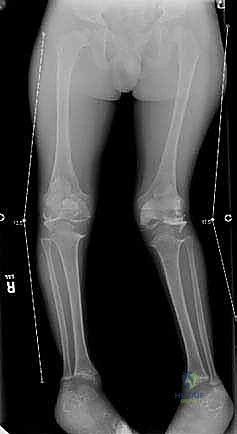

1. الركبة الروحاء (Genu Valgum - Knock Knees)

تُعرف شعبياً بـ "تلاصق الركبتين". في هذه الحالة، تتلامس ركبتا الطفل معاً بينما تتباعد قدماه وكاحلاه بشكل ملحوظ عند الوقوف.

شكل 1 • أ. يعاني هذا الصبي البالغ من العمر 13 عاماً من السمنة والركبة الروحاء مجهولة السبب مع زيادة المسافة بين الكاحلين وعدم استقرار الرضفة. بدون تدخل جراحي دقيق لإعادة تنظيم الطرف، فإن التاريخ الطبيعي يشير إلى تدهور حتمي في وظيفة الركبة.

التقييم الإشعاعي (الأشعة السينية)

لا يكتمل التقييم السريري دون صور أشعة دقيقة. يطلب الدكتور هطيف صورة أشعة سينية طويلة للساقين بالكامل (من الورك إلى الكاحل) أثناء الوقوف (Standing Long-Leg X-rays). من خلال هذه الأشعة، يتم رسم خط المحور الميكانيكي، وحساب زوايا دقيقة جداً (مثل mLDFA و MPTA) لتحديد مركز التشوه بدقة متناهية، سواء كان في عظمة الفخذ، أو القصبة، أو كليهما.